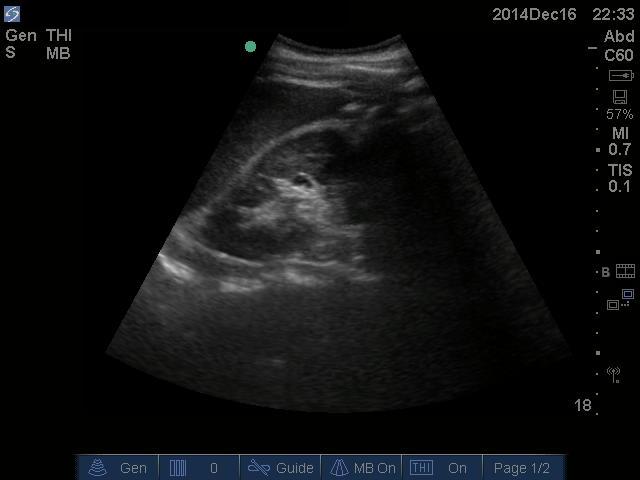

FAST showing no free fluid found here:

All U/S images are courtesy of McMaster PoCUS Subspecialty Training Program.